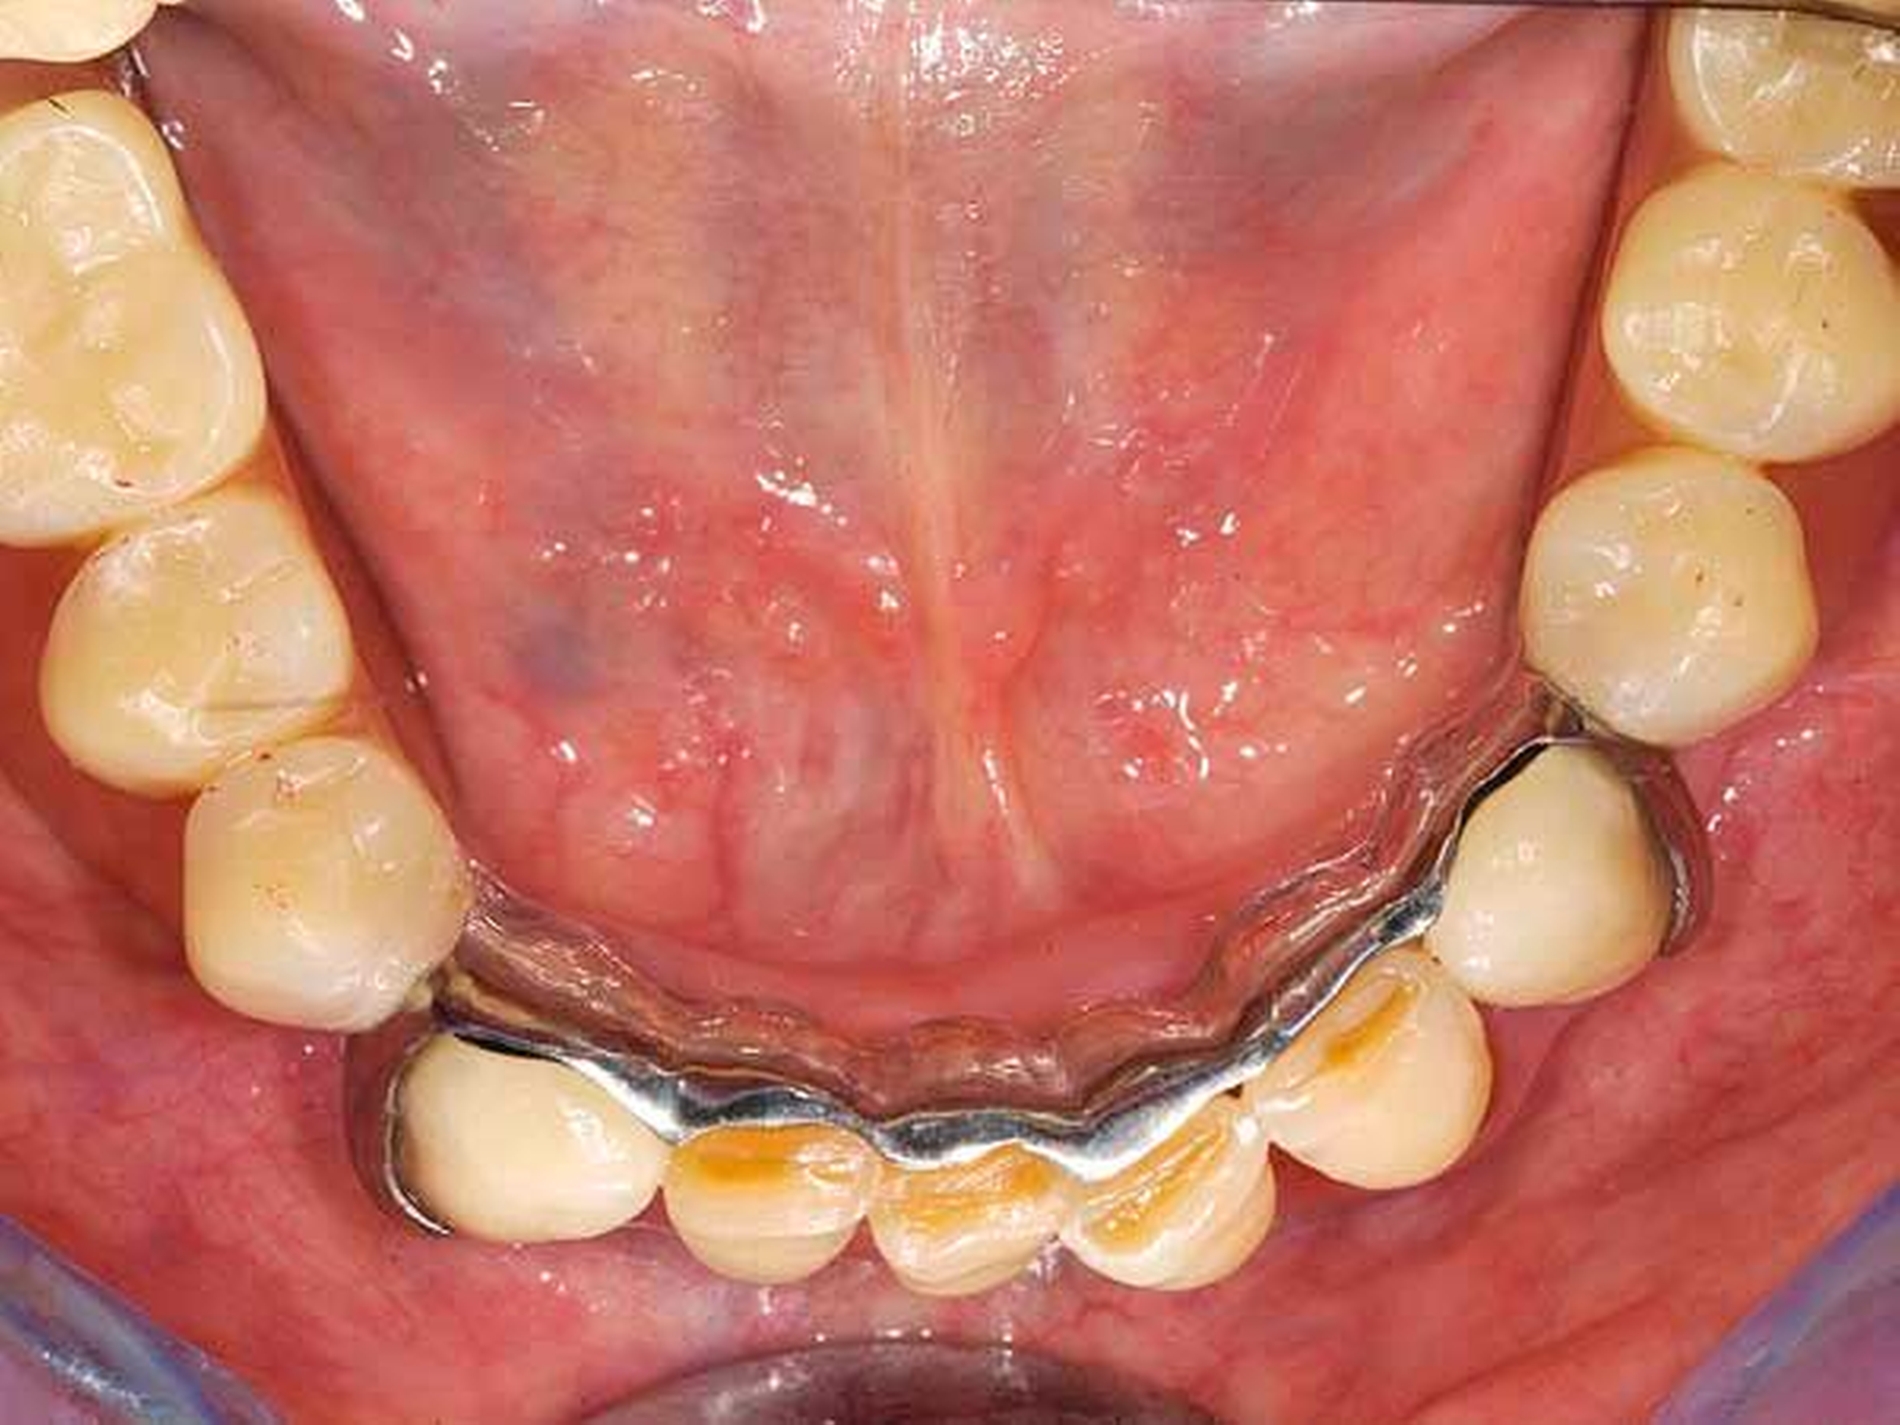

Front- und Eckzähne sind aufgrund ihrer Anatomie grundsätzlich schlecht für die Aufnahme von Gussklammern geeignet. Die Lösung in diesem zweiten Fall bestand in der Anwendung zweier geteilter Klammern (Roach-Klammer), ausgeführt als Druckanker (Abbildungen 9 und 10). Lingual wurden die Zähne 33 und 42 mit den oralen Klammerarmen großflächig von disto- nach mesioapproximal gefasst. Gegebenenfalls müssen, nach Augenmaß senkrecht zur Einschubrichtung, die Tuberculi und der distoapproximale Kontaktpunkt im Schmelz mit einem Diamantfinierer leicht abgeflacht werden. Die Präparation für die orale Klammerauflage in Höhe der Tuberculi muss konsequent als Stufe von 1 mm Tiefe parallel zur Okklusionsebene eingeschliffen werden. Die Auflage selbst ist in den oralen Klammerarm integriert. Die vestibulären Retentionsarme liegen dem Zahn nicht passiv an, sondern stehen unter Vorspannung und drücken den Ankerzahn bei eingegliedertem Zahnersatz aktiv gegen das starre Widerlager der oralen Umfassung. Dies sichert in Verbindung mit der weiten, fast geschiebeartigen oralen Fassung und der integrierten Klammerauflage eine akzeptable Kippmeiderfunktion.

Die großflächigen Umfassungen der oralen Ankerzahnflächen erhöhen das Kariesrisiko, dem kann mit adäquater Mundhygiene und Fluoridierung begegnet werden. Zur Optimierung der parodontalen Hygienefähigkeit wurden die Regeln der „Grenzraumgestaltung nach Marxkors“ (brückenzwischengliedartige Gestaltung des ersten Prothesenzahnes mit metallischer Basis, Durchspülbarkeit, Insertion des sublingualen Bügels in den Sattel eine Prämolarenbreite hinter dem endständigen Zahn [Marxkors, 2007]) konsequent umgesetzt (Abbildungen 11 und 12).